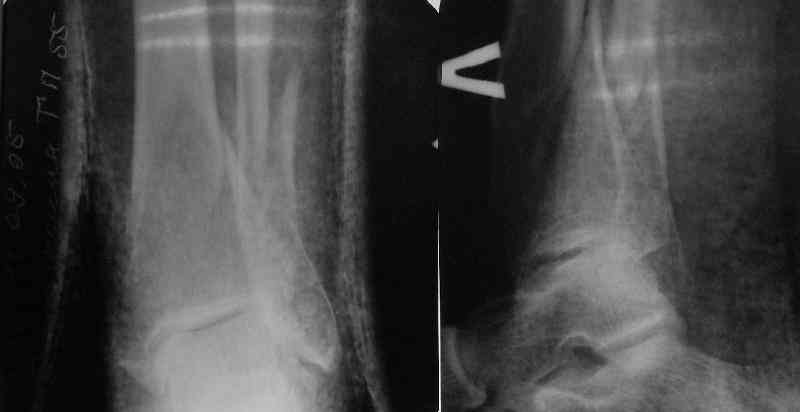

A typical case is attached, also an image with intra-op reduction obtained by a small wire distractor, in the moment of insertion a Poller wire in AP direction. Fixation by a SIGN nail. Despite the fibula was not fixed healing was obtained with the unchanged alignment.

Very interesting application, but is the final position in a little distal varus with some fibula

distraction? Would that have been eliminated by fibula plating?

TDVC> little distal varus with some fibula distraction?

At least both the ankle mortise and tibial alignment look acceptable, don't they?